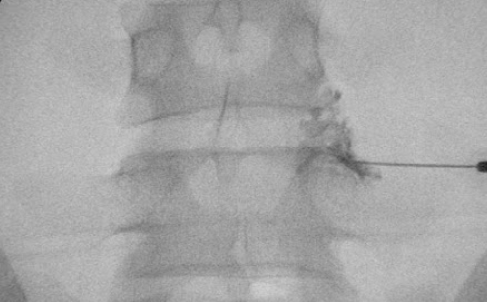

STEP1

위치확인

STEP2

바늘진입